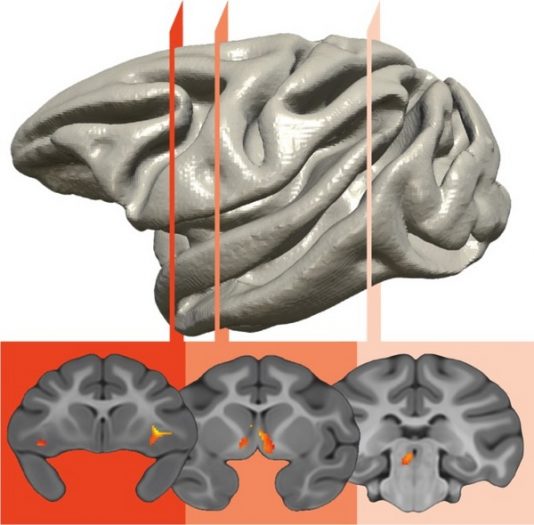

محققان مغز میمون‌های جوان را اسکن کرده و دریافتند مناطق مغزی مرتبط با اضطراب در این حیوانات، شواهدی از ارثی بودن را به نمایش گذاشتند. حدود ۳۰ درصد از اختلافات در اضطراب زودرس با تاریخچه خانوادگی توضیح داده می‌شوند.

آنها از اسکن PET برای تصویربرداری از مغز ۵۹۲ میمون رزوس جوان استفاده کردند. این میمون‌ها بصورت جفتی در مرکز ملی تحقیقات ویسکانسین نگهداری می‌شوند.

محققان همچنین دریافتند که عملکرد سه منطقه مغزی قشر اوربیتوفرونتال، آمیگدال و سیستم لیمبیک، قابل توارث بوده و در اضطراب دخیل هستند.